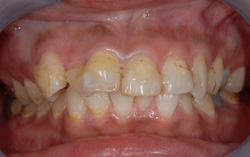

審美歯科症例 Y.Aさん(18歳女性)

治療前 治療後 上顎前歯4本をオールセラミックで修復しました。 年齢・性別 18歳 女性 治療費 440,000円(税込) 治療期間 1ヵ月 通院回数 3回 リスク・注意点 ブラッシング圧が強すぎますと、歯肉が退縮するこ […]